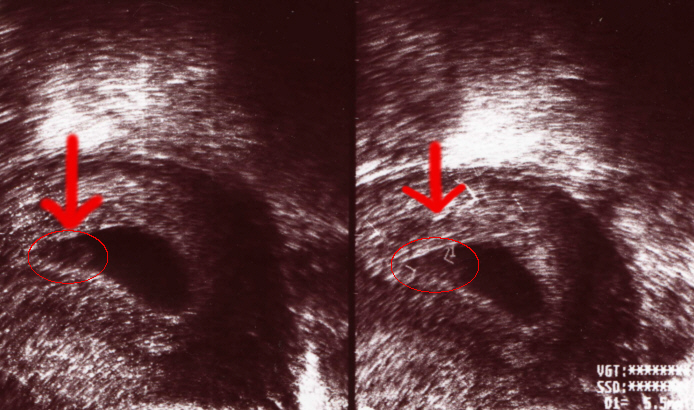

Hier ist die Fruchtblase (der schwarze Fleck) zweimal fotografiert.

Der gräuliche Punkt (rot umrandet) im schwarzen Fleck ist Ivo. Er ist hier circa 6mm groß.